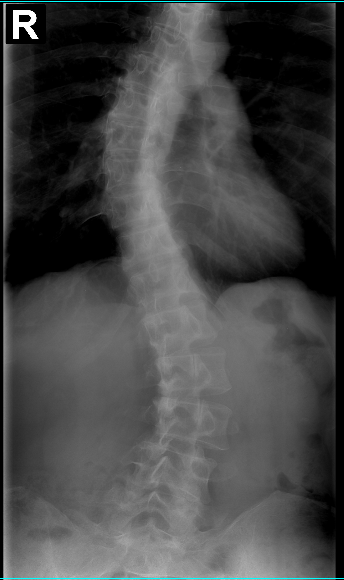

Frequently, the Schroth Method is referred to as a three-dimensional treatment technique. Scoliosis causes the spine to compress, shift, and rotate. It is a pathology that occurs in three planes. This technique, a unique approach, works on the transverse, sagittal, and coronal planes of the body. The exercises achieve the optimum result when all the pathological spinal deformities are addressed at the same time. The exercise methodology is built to elongate the spine, shift, and de-rotate it to balance the posture.

Curve-specific movements, mental imaging, and body awareness also play significant roles in posture corrections. Specific breathing patterns are especially important for correcting the curvature through rib movement.